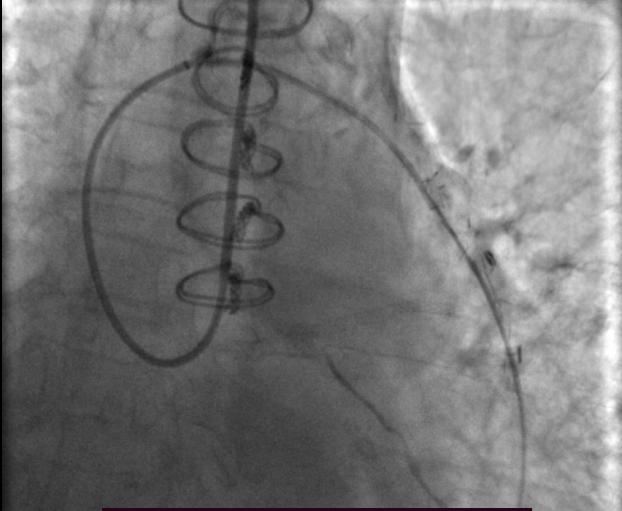

圈套器成功抓捕RG3导丝

静脉桥恢复TIMI 3级血流,并可见向LCX供血,显影良好